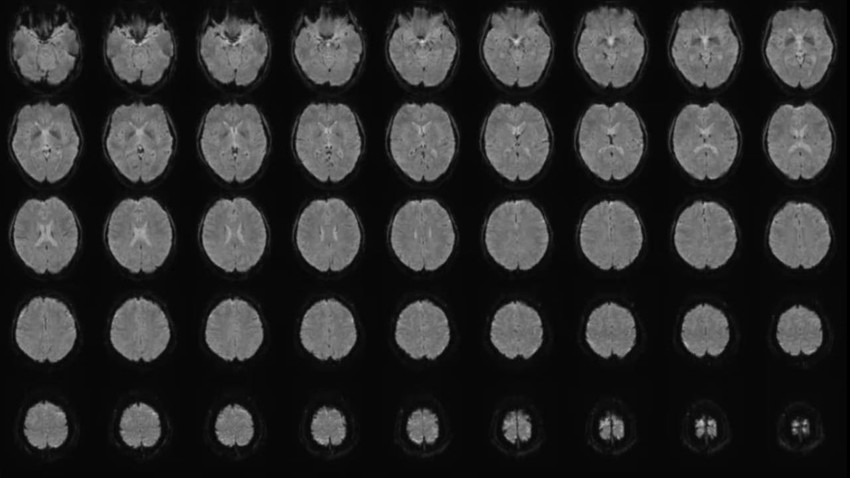

CNN International'ın haberine göre araştırmada, 22-37 yaşları arasındaki altı katılımcının beyin aktiviteleri, sessiz videolar izlerken tarandı. AI, bu videoların açıklamalarını sayısal dizilere dönüştürdü ve Horikawa, taramalardan elde edilen verileri bu dizilerle eşleştiren ayrı “dekoder” modelleri geliştirdi. Dekoderler, katılımcılar yeni videolar izlerken veya hatırlarken beyin aktivitelerini çözümleyerek metin üretmeyi başardı.